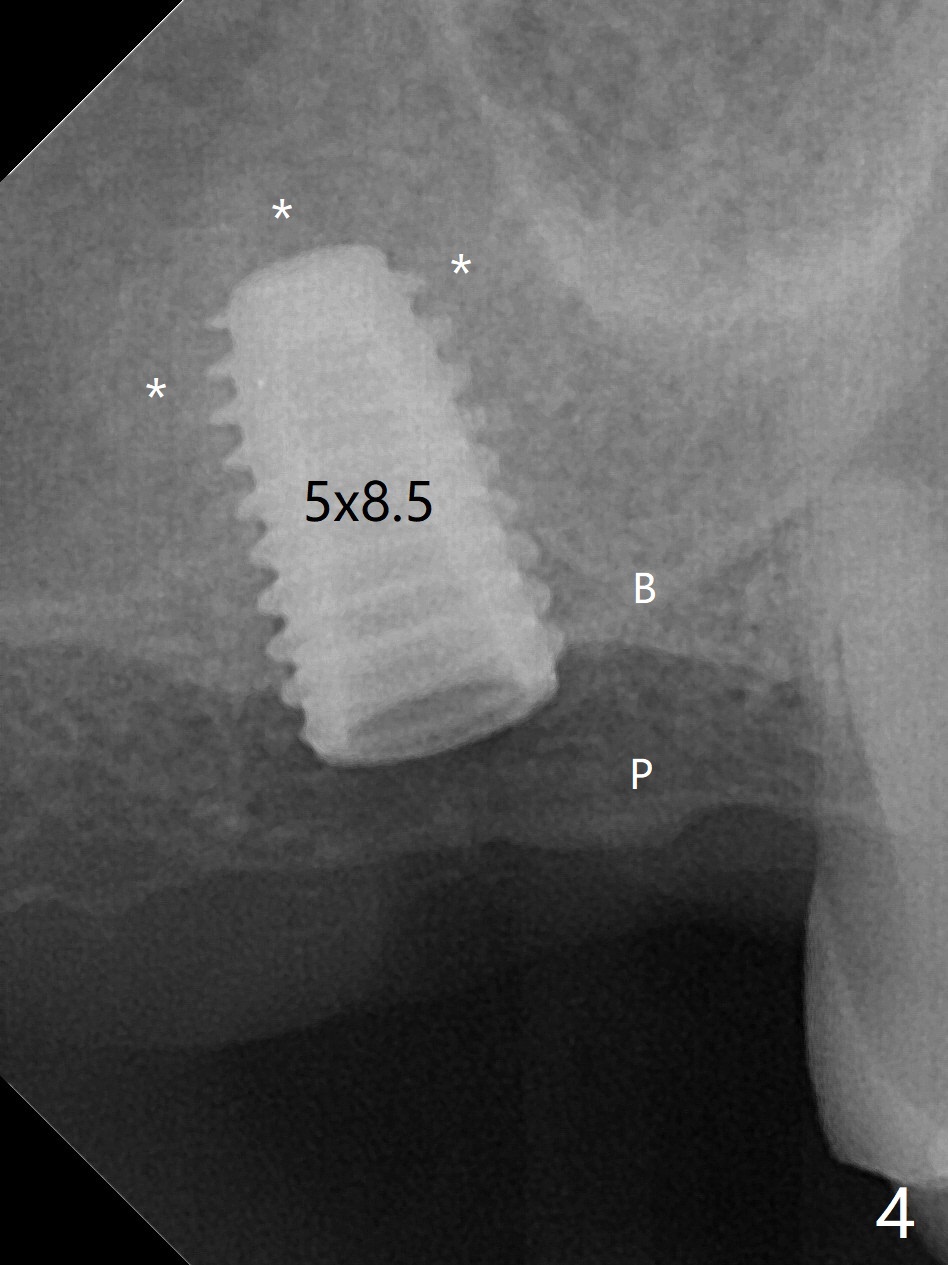

尽管事先准备15号刀片,看到完整2号牙牙槽嵴就舍不得切开。放置以前导板(用于即种),用软组织环形刀做个记号,接着用活检环形刀切取钻洞表面软组织,保存于PRF液体中。术前CT显示3号牙上方粘液囊肿(图一:*),而2号牙上方窦膜薄,总之两者都不好惹(容易感染,窦膜破),提升需要特别小心。完成初步钻洞后,使用17-19毫米长的DIO圆钻,放置粘性骨粉,使用4.5x10毫米报废植体进行提升(到第一横线),结果窦底没有穿(图二:红箭头)。接着使用尖头钻头从原来2.2x5.3毫米一直到3.5x10毫米,几乎每使用一个钻头后都检查窦底完整性,再放置骨粉,使用4.0x10毫米植体提升(到第二横线),好像穿过窦底(图三)。再加骨粉,使用4.5x10毫米植体扭力底,最后放置PRF膜,很难塞入上颌窦,结果只能从钻洞上端近中很小裂口塞入,植入5x8.5毫米正式植体(图四),上颌窦里骨粉呈蘑菇状(*)。临床检查腭侧(P)植体牙槽嵴下,其余骨壁难于判断。而咬翼片却显示植体颊侧(B),腭侧均在牙槽嵴下(图五)。为了减少术后骨质吸收,放置愈合螺帽后(图六:S),植体表面添加骨粉(*),最终把保存的软组织放回原位(二期手术:减少上颌窦与口腔交通,感染),牙周胶水粘固(图七)。术后没有鼻出血。